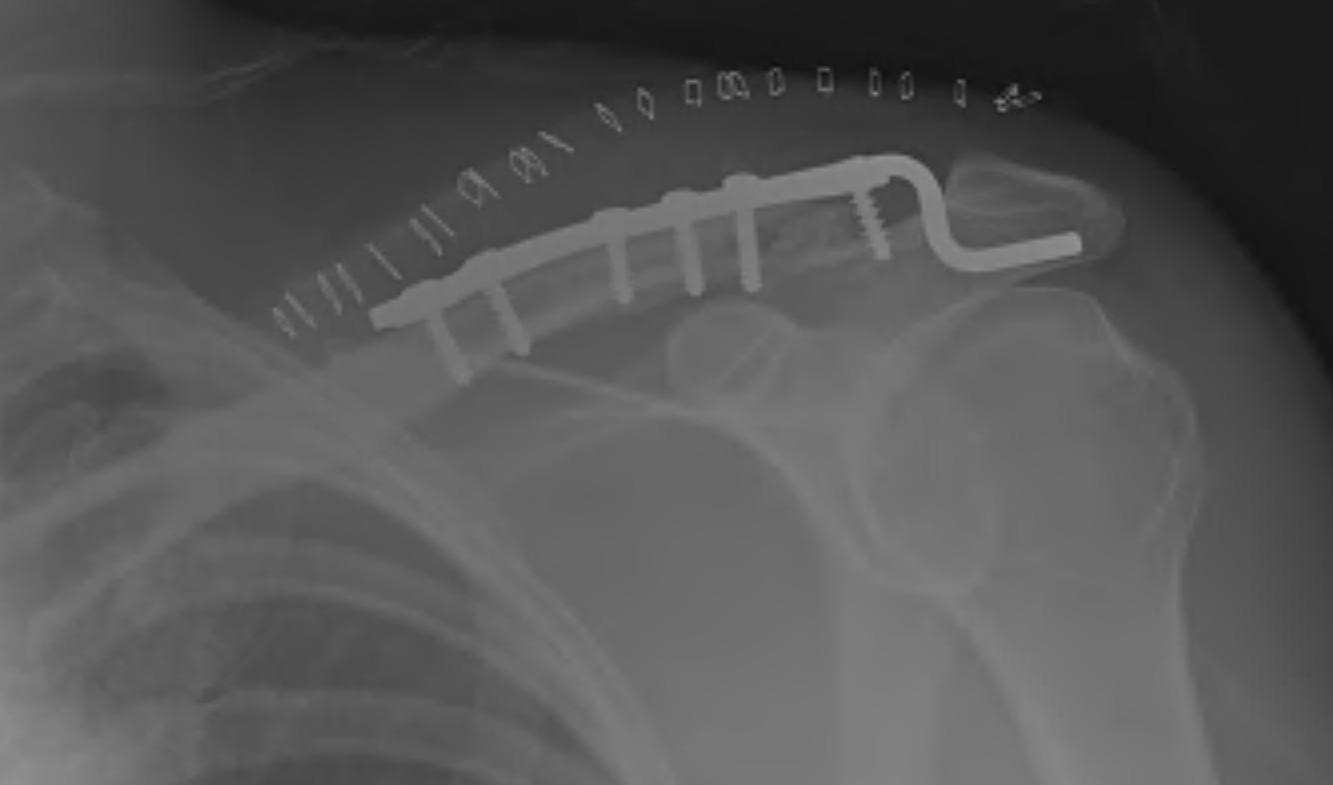

Hook Plate

Advantage

Mechanically secure

Disadvantage

Needs to be removed

- subacromial impingement

- acromial erosion

- shoulder stiffness

Lazy beachchair

- tilt head away

- split delto-trapezius fascia to expose clavicle

- clean and reduce fracture

- detach trapezius from medial acromion to facilitate hook passage under acromion

- trial different hook depths +/- image intensifier

- avoid over-reduction / insufficient hook depth increases risk of acromial erosion

Results

- 36 patients with displaced distal clavicle fractures treated with hook plate

- 95% union rate

- mean time to union 3 months

- hook plate removed in 92%

- 2 patients presented with late falls and fractures medial to the plate

- 35 patients with displaced distal clavicle fractures treated with hook plate

- 100% union rates

- 23% shoulder stiffness

- 17% subacromial erosion

Complications

Hook not under acromion Periprosthetic fracture